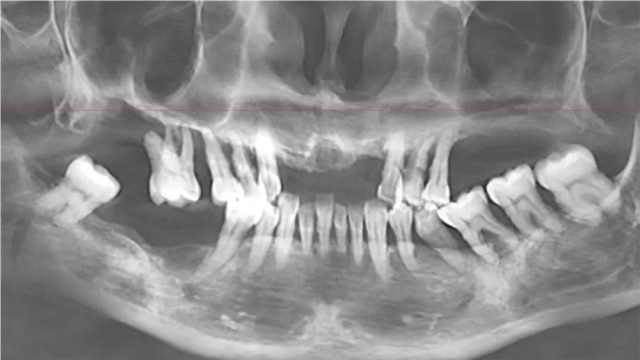

70岁的刘先生口腔状况较好,目前只有一颗缺牙,他与安女士同日完成了种植手术。从进手术间到完成手术,整个过程不到20分钟。李阳军医生说,虽然只缺了一颗牙,但影响范围并不局限于这一颗,如果让它一直缺着,会影响咬合,还会造成食物嵌塞,对其他牙齿也有影响。

“种上这颗牙的意义,不仅是恢复了它的咀嚼功用,还挽救了两边的邻牙,避免了长期缺牙后邻牙的倾斜,也避免了对侧的牙齿出现伸长。”据介绍,刘先生牙槽骨条件比较好,通过上颌窦上提1毫米,没有植骨就顺利完成了种植体的埋入。